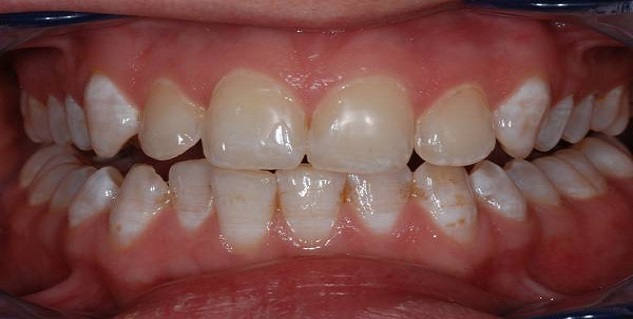

फ्लोरोसिस का मुख्य लक्षण दांतों पर सफेद, पीले या भूरे धब्बे हैं। कई बार ये धब्बे इतने हल्के होते हैं कि ध्यान देने पर ही दिखाई देते हैं या चिकित्सक की जांच में नजर आते हैं। हालांकि फ्लोरोसिस इसलिए खतरनाक है क्योंकि समय के साथ ये धब्बे और इनका रंग बढ़ता जाता है इसलिए सही समय पर इसका इलाज जरूरी है।

ज्यादा फ्लोराइड के इस्तेमाल से फ्लोरोसिस हो जाता है जिसमें दांतों का रंग हल्का हो जाता है या दांतों की सतह पर अनियमितताये पैदा हो जाती हैं । एक बार दांत पूरी तरह से विकसित हो जाता है तब उसपर ज्यादा फ्लोराइड का प्रभाव नहीं पड़ता। फ्लोरोसिस दांत की बीमारी से ज्यादा कॉस्मेटिक समस्या है। कई मामलों में यह इतना हल्का होता है कि इसे डेंटिस्ट हीं पहचान सकते हैं। पीने के पानी में पर्याप्त मात्रा में फ्लोराइड होने के बावजूद अगर बच्चे फ्लोराइड की अतिरिक्त खुराक (दवा या टूथ पेस्ट निगलने के रूप में लेते हैं) तो उन्हें फ्लोरोसिस हो सकता है।